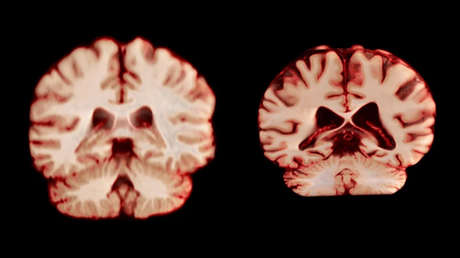

Durante la investigación se reunieron más de 12.500 escáneres cerebrales de participantes de entre 17 y 95 años, recopilados a lo largo de los años. Cada individuo se sometió al menos a dos resonancias magnéticas cerebrales, con un intervalo medio de aproximadamente tres años entre ellas.

Tras examinar las diferencias de tamaño cerebral basadas en el sexo, el equipo descubrió que los hombres mostraban un deterioro en un mayor número de regiones cerebrales, incluidas muchas partes de la corteza, a edades más avanzadas.